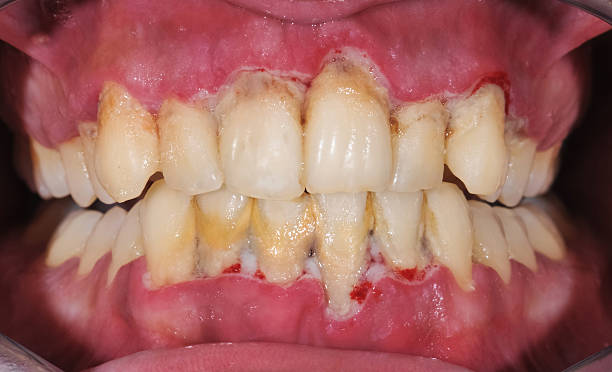

-초기 치주염 : 잇몸이 붓고 들뜬 느낌이 나고 빨갛게 붉어지고 건드리면 피가 납니다.

-중기 치주염 : 잇몸이 내려가고 이 사이가 벌어지며 치아가 약간씩 흔들리기 시작합니다.

-진행된 치주염 : 잇몸이 심하게 내려가서 치아 뿌리가 보이고 치아 사이가 벌어지며 흔들립니다.